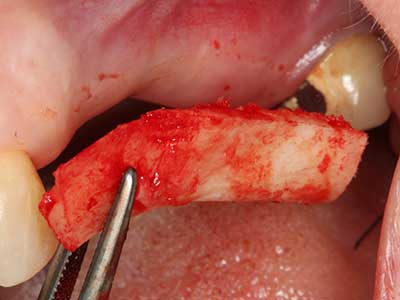

Fig. 4: mediante l'ablatore osseo si raccolgono ulteriori microframmenti dell'osso autologo.

Fig. 5: verifica delle dimensioni del blocco nel sito ricevente.